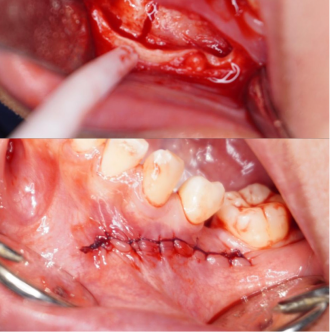

Before dan After pencabutan gigi di dentalogy